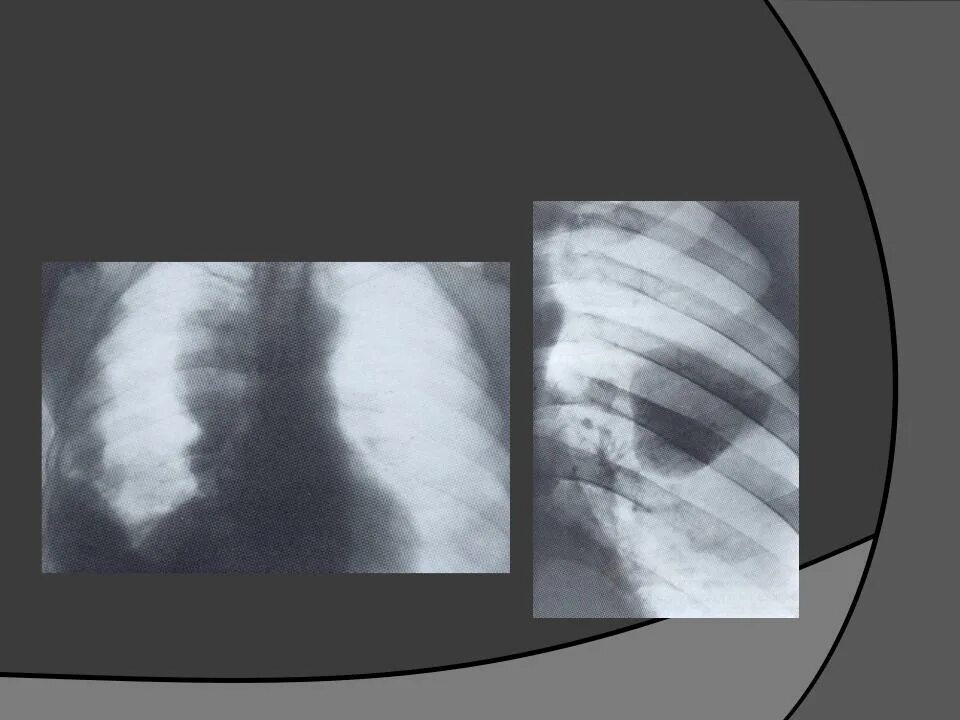

Бронхоаденит это